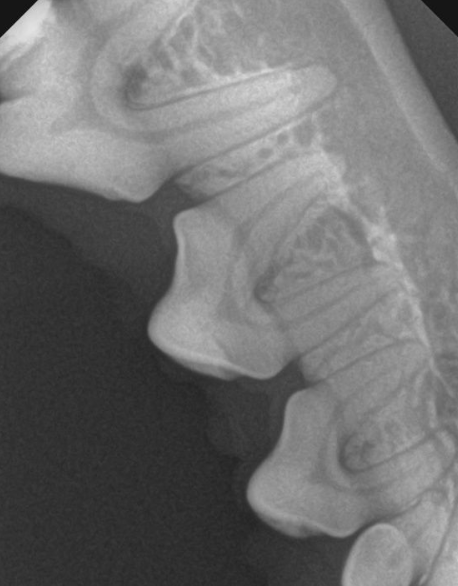

这是洗牙过程中拍的片子